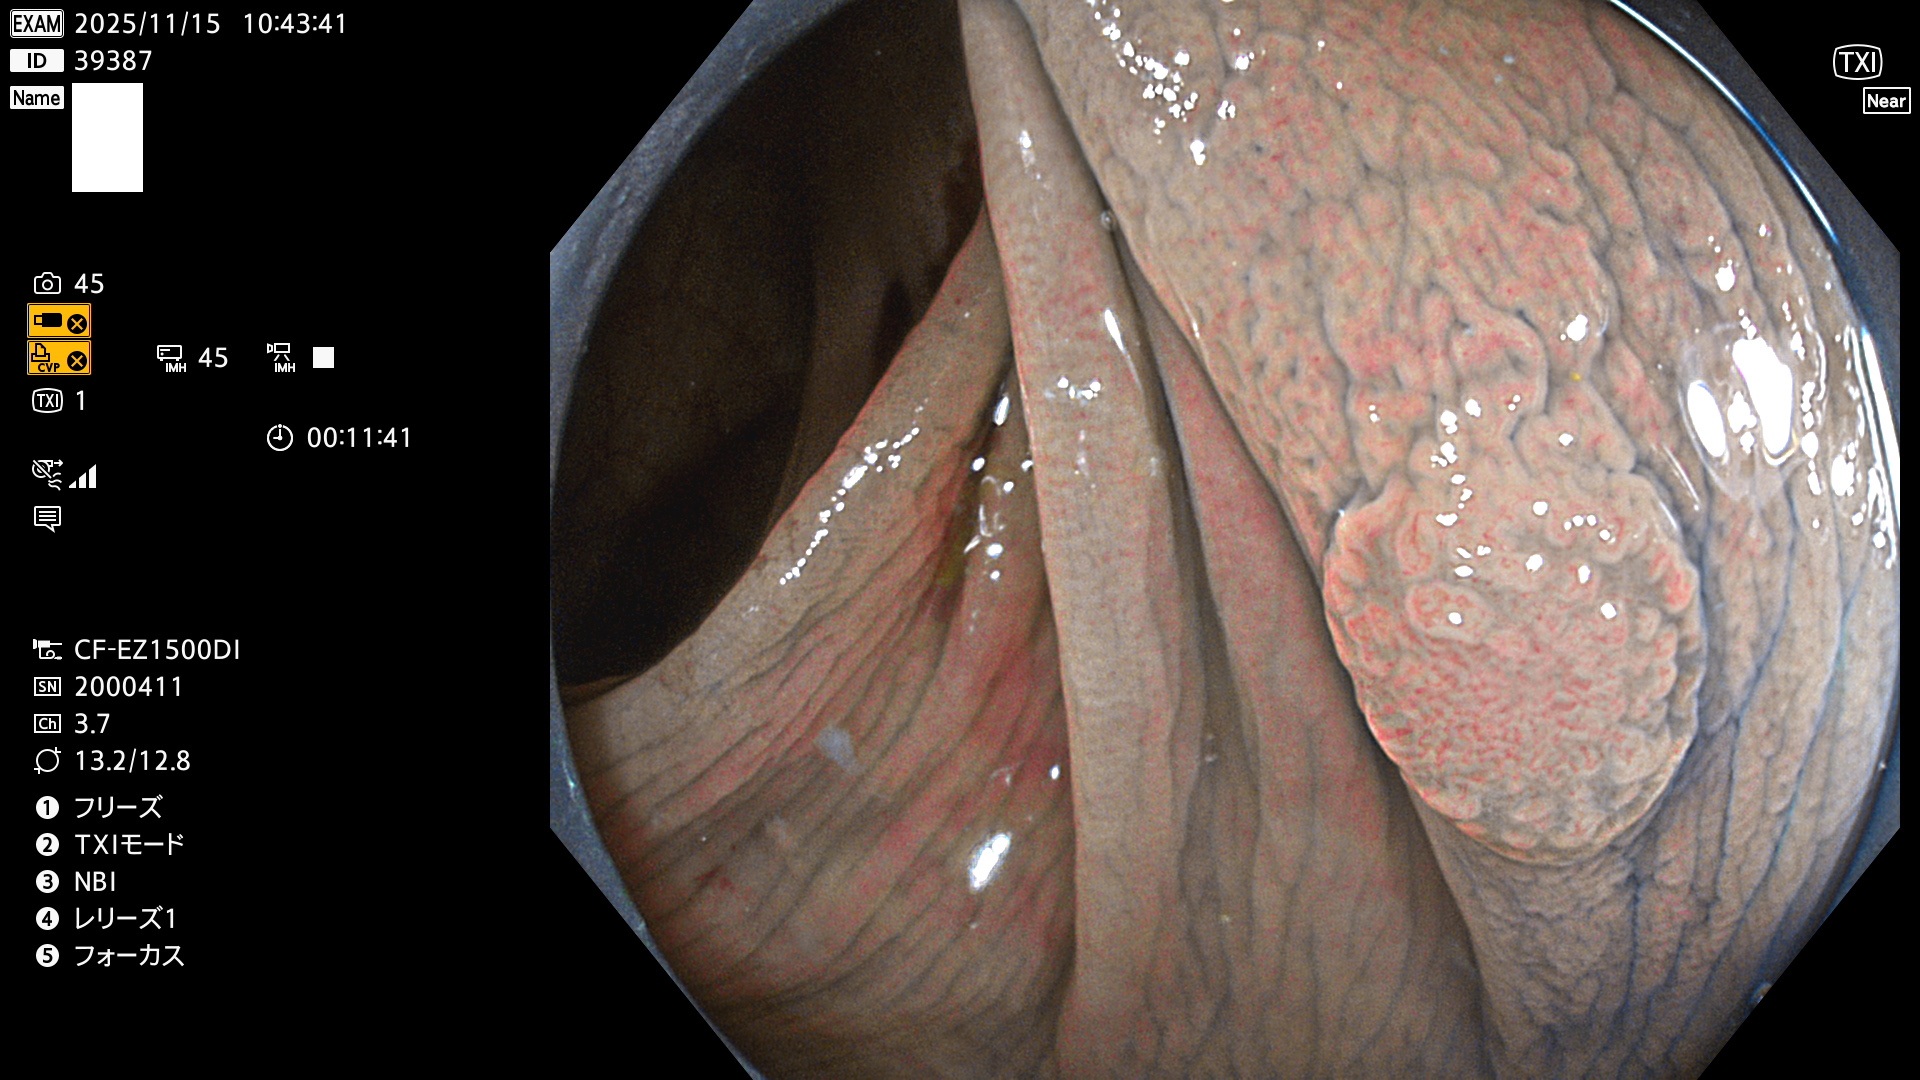

完全に平坦な物をUb、陥凹している物をUcと呼びます。Ubは認識が困難で、Ucはびらん(炎症)と紛らわしいために見落とされやすく、「内視鏡後・大腸癌」の原因になります。

毎週の検査(木・金・土・日)に発見されたUbとUc型・腺腫を、その週の日曜の夜にUPし1週間、提示します。

2025年11月13日〜11月16日の4日間(40件)4個 (Uc_ADR=4個/40人=10%)